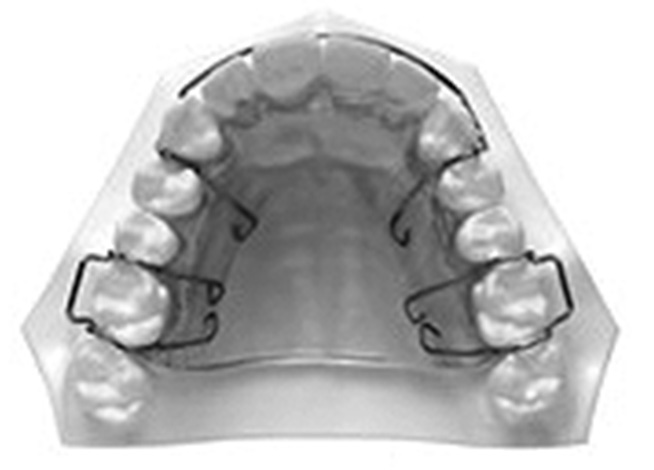

У пациентов с сочетанной патологией окклюзии зубных рядов с применением брекет-системы перед ее удалением из полости рта фиксировались несъемные проволочные ретейнеры на внутреннюю поверхность фронтальных зубов (рис. 3) и каппы (рис. 4).

Рис. 3. Несъемный проволочный ретейнер.

Fig. 3. Fixed wire retainer.